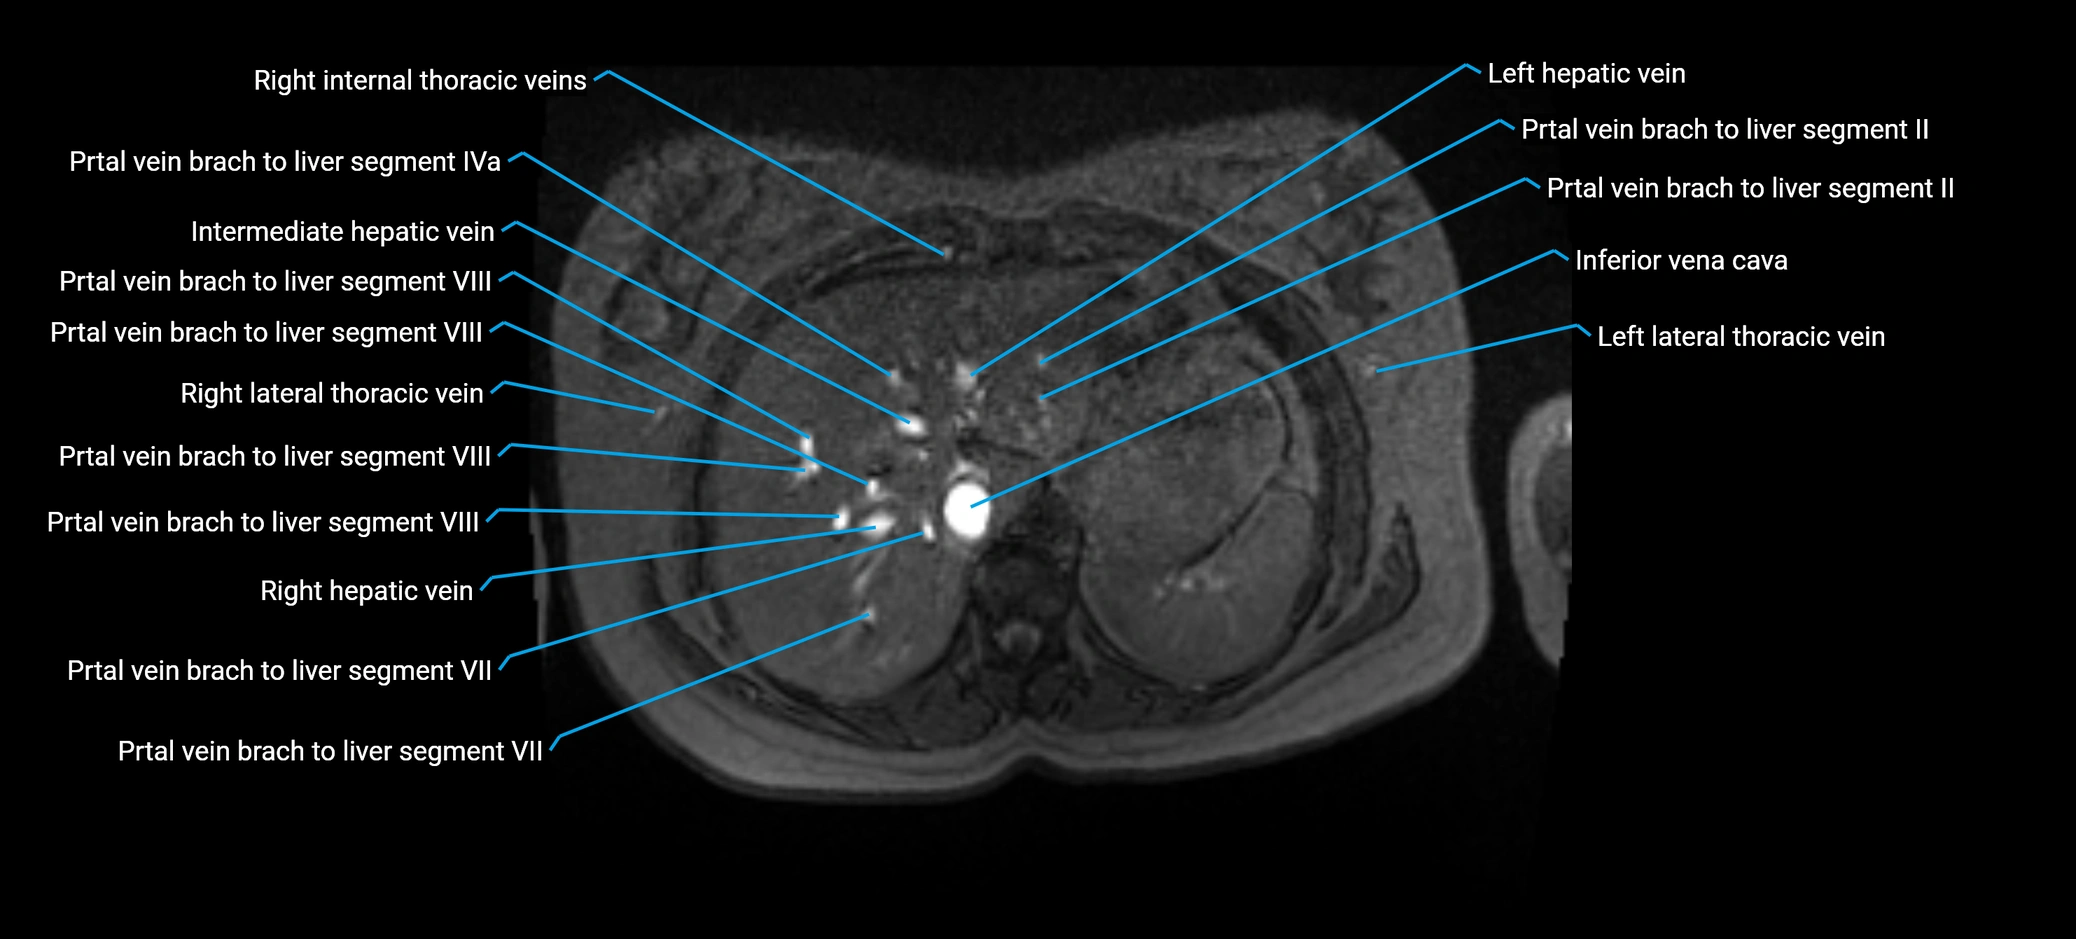

MRV TOF (Time-of-Flight MR Venography):

• Appears as a bright, high-signal vascular channel representing flowing blood

• Clearly shows branching pattern of right portal vein into anterior and posterior branches

• Best in coronal or axial reconstructions for segmental mapping

• No need for contrast, relies on flow-related enhancement

T2-weighted MRI:

• Flowing blood within the anterior right portal vein appears as dark flow void

• Hepatic parenchyma appears moderately bright

• Excellent for visualizing course and anatomic relationships

• Biliary radicles appear brighter, helping vascular-ductal differentiation